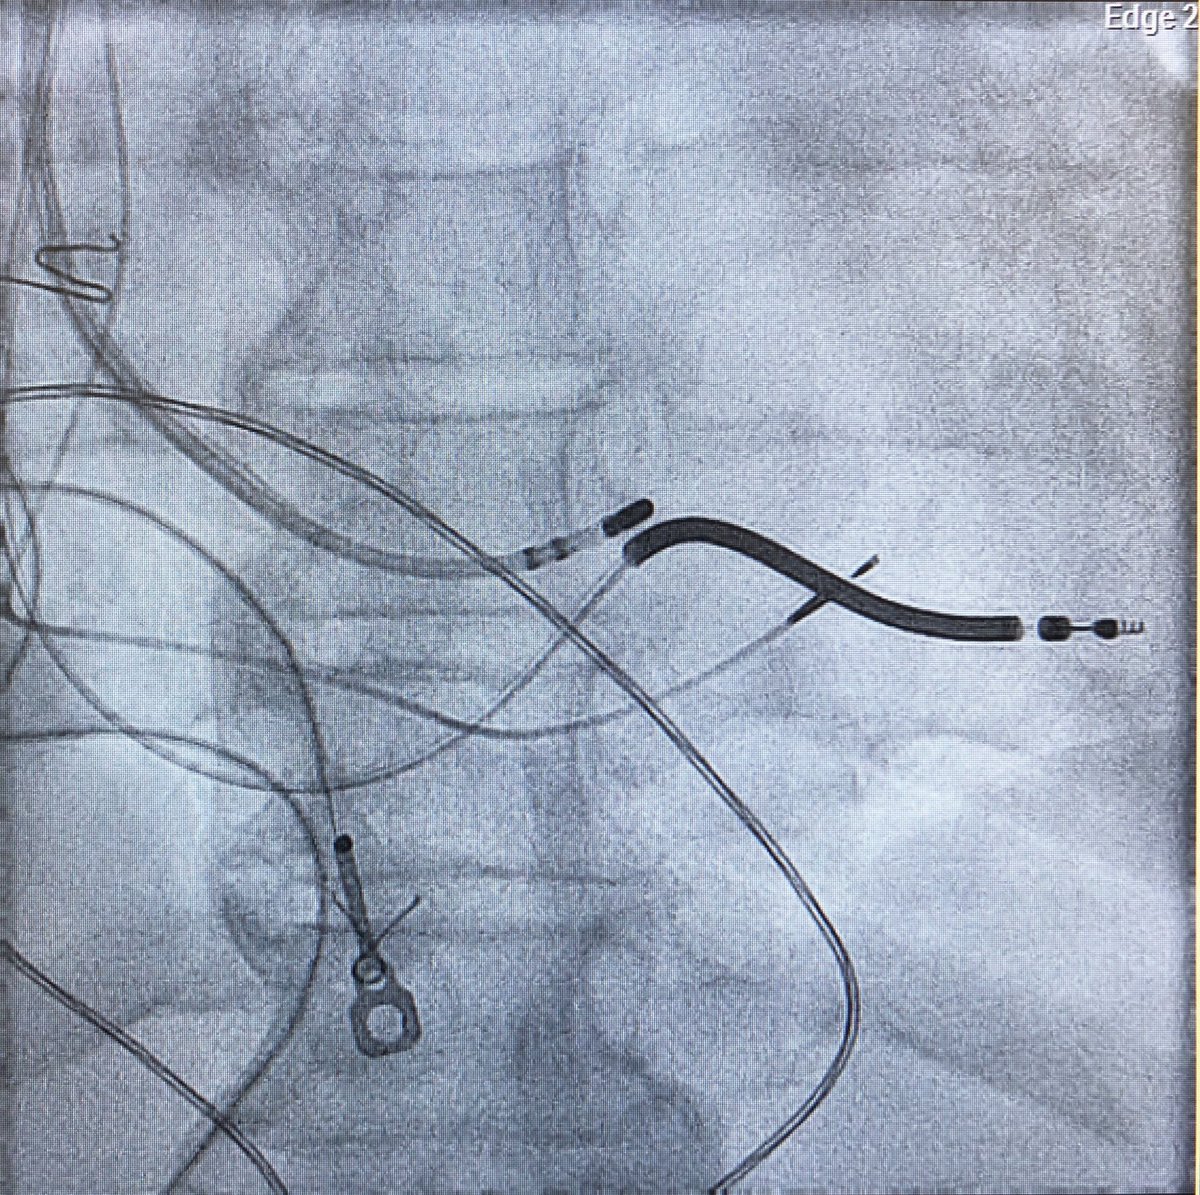

31 yo man. Antidromic ART mimicking OFT VT. Anyone seen/heard of accessory pathway to R-L SOV before? Slowly conducting and pathway potential 82 ms pre-QRS. One burn! Fun case/maneuvers. #EPPeeps @ReddyEPS @DrRigoRamirezEP @DrGregMichaud @jaymontgomery44 @DrRoderickTung @ @KUCVM

11

24

67